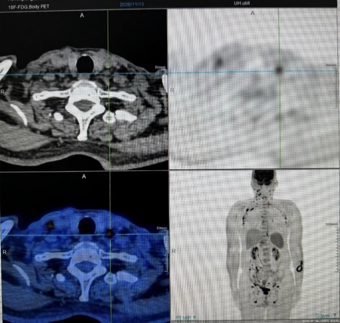

多个淋巴结受累:包括双侧颈部、锁骨区、膈上、双侧腋窝、腹腔及腹膜后、盆腔及双侧腹股沟区淋巴结增大,最大者直径为20.0mm,最大标准化摄取值(SUVmax)为14.4。淋巴结性质尚待进一步评估。

-

脾脏增大,SUVmax为3.8。

可能存在多发炎性皮肤病变,尚待进一步评估。 -

结直肠存在多个糖代谢异常增高灶,建议进行肠镜检查以排除恶性肿瘤(MT)(患者因高龄拒绝行肠镜检查,后续随访CT检查提示此部位为炎性改变)。

双肺存在慢性炎症及陈旧病灶。